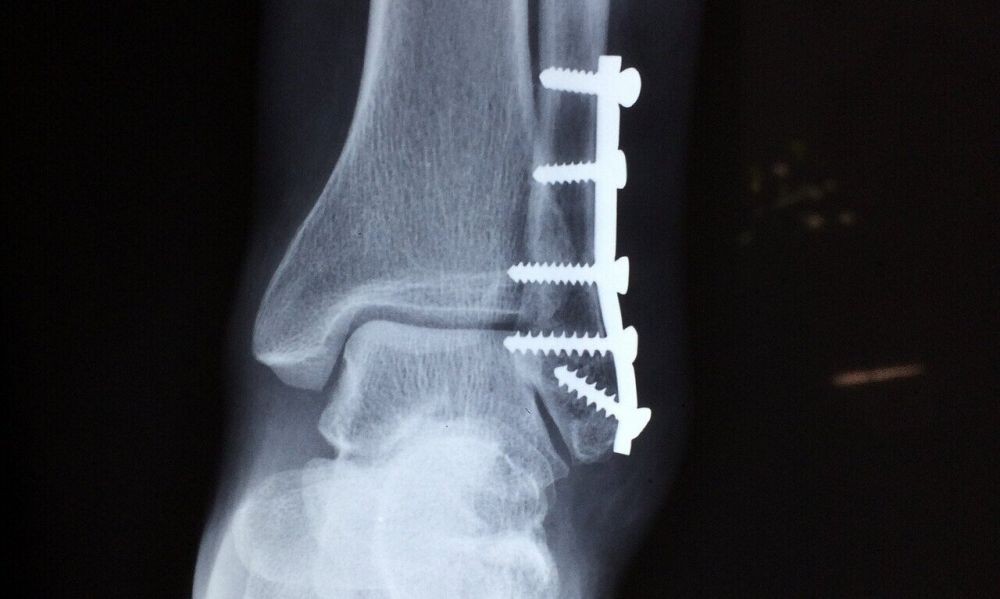

Perlukah membuang besi atau implan? û Dr Ahmad Mahyuddin | The Malaysian Medical Gazette

Perlukah membuang besi atau implan? û Dr Ahmad Mahyuddin | The Malaysian Medical Gazette

Plat Logam Pasca Fraktur : Perlu Diangkat Atau Tidak - Alomedika

Plat Logam Pasca Fraktur : Perlu Diangkat Atau Tidak - Alomedika